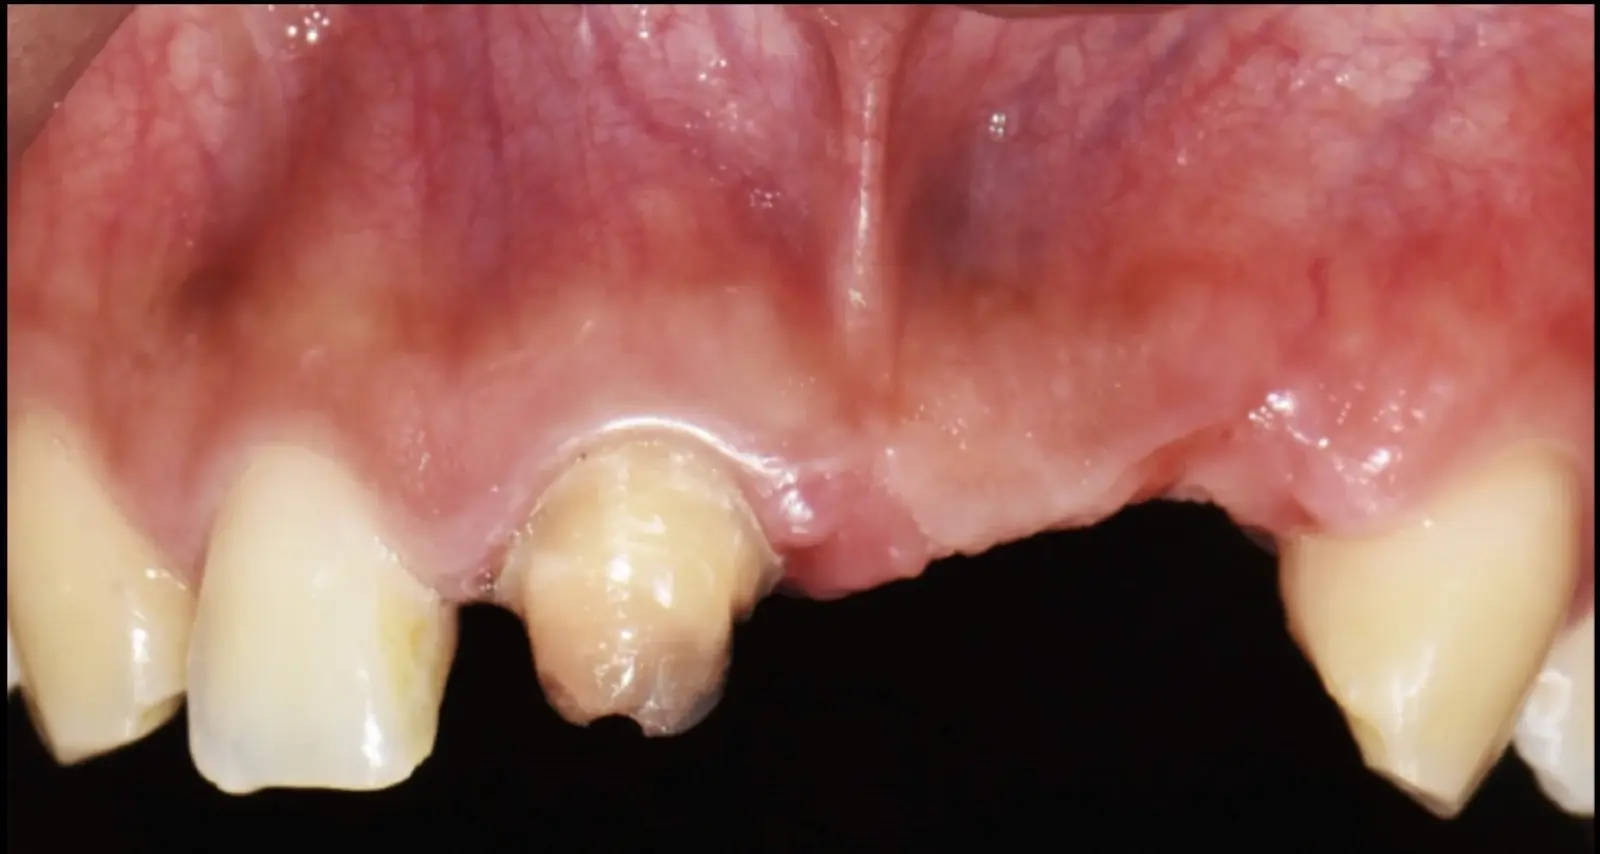

Paciente de sexo femenino de 36 años de edad, llega a la consulta por presentar una restauración protésica inadecuada. En el examen clínico se observa una restauración protésica provisional acrílica sobre las piezas 1.1 y 2.2. Adicionalmente, se aprecia recesión gingival a nivel de la pieza 2.2 y deficiencia horizontal severa de reborde a nivel de la zona edéntula correspondiente a la pieza 2.1. En la evaluación tomográfica se observa ausencia total de tabla ósea vestibular en la pieza 2.2, y se corrobora el déficit en la zona edéntula de la pieza 2.1, para lo cual se indica una reconstrucción de estructuras óseas con hueso en bloque de origen bovino y posteriormente la colocación de implantes dentales.

Figura 34. Vista frontal donde se observa deficiencia vertical del reborde óseo a nivel de las piezas 2.1, 2.2.